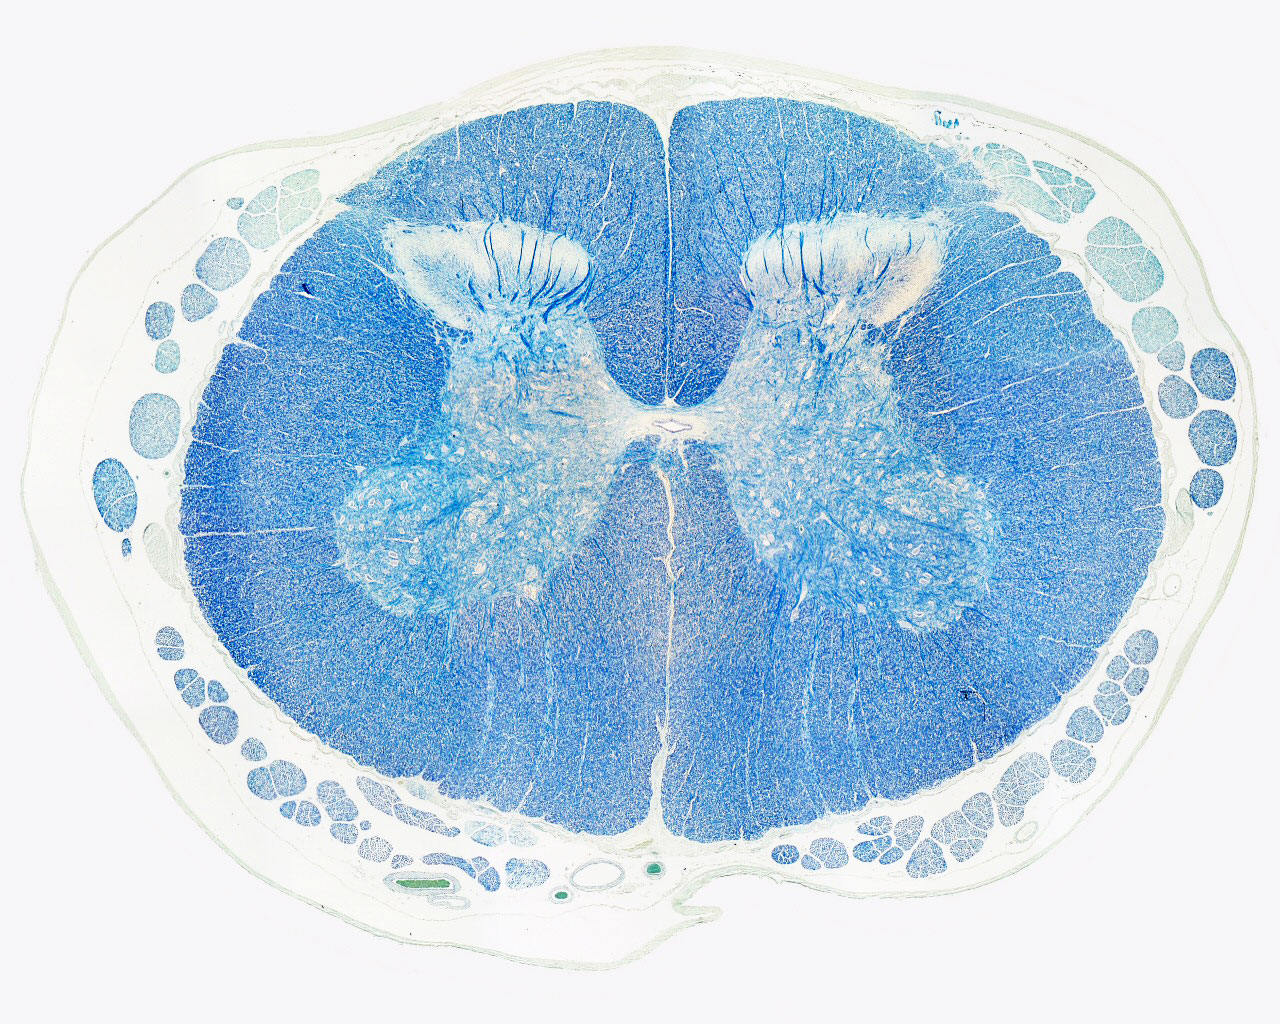

Know your spinal cord – The landmarks

A human cervical spinal cord slice. Once you’ve read this post, you should be able to identify the major parts and tell which side is the front of the cord.

Welcome to day thirty-three in our series. For those of you who are just finding us, we have every one of these posts in our neuroanatomy category in reverse chronological order. Today we’re going to backtract (get it?) a little and go over something basic, but something we’ve skipped over to this point. We never really talked about the landmarks of a spinal cord slice. So today, we are going to take a detour and go over spinal cord features.